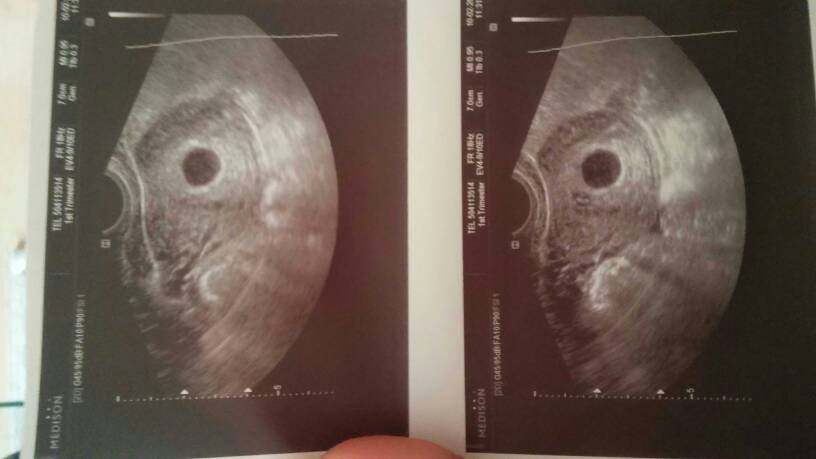

Dziewczyny, gadalam z moją mamą i mówi, że ze zdj albo puste jajo albo ciaza tydzień młodsza jak nie lepiej i nie widać. Teoretycznie 6tyd 3 dzień, ale tak to już by było widać dawno. Dziewczyny z pustym jajem, tak mialyscie?

Pokaz mi te usg bo ja nie widziałam forki.

1486762828-aaaaaa.jpeg